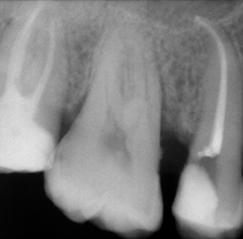

Due to the controlled memory, the files always follow the anatomy of the canal, thus significantly reducing the risk of ledging, transportation or perforation of a canal. Like stainless steel files, the HyFlex EDM files can be pre-bent.

This is a crucial advantage in extremely curved root canals to avoid the creation of steps.

Dr. Richard Gray

Dr. Byron Tsivos